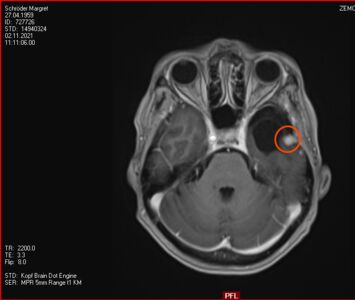

12. November 2021: Innerhalb der Messungenauigkeit

Heute war ich mit Stephan in der Ambulanz der Neurochirurgie zur Auswertung des MRTs, dass vor 10 Tagen erstellt wurde. Das Ergebnis ist erfreulich:

• der Tumor ist sehr klein (< 10mm) und deshalb stört er  nicht

• der Tumor ist, wenn überhaupt, sehr wenig gewachsen und so genau misst das Gerät nun auch nicht (vielleicht habe ich nicht still gelegen?!)

• durch die Gamma-Knife-Bestrahlung kann man das Wachstum des Tumors beschränken, die Strahlen entfernen ihn nicht

• falls doch mal Wachstum auftreten sollte, sitzt das Ding an einer guten Stelle und aus Sicht des Neurochirugen ist es "im Notfall" nur eine kleine Sache ihn zu entfernen

Also alles prima, alle Aufregung unnötig. Ich lebe nun halt mit einem Tumor im Kopf weiter und lassen ihn in 6 Monaten neu inspizieren. Ich bin erleichtert, es geht mir prima und auch die Schulternschmerzen haben sich verzogen. Gestern konnte ich auch schon wieder 15km langsam joggen.

2. November 2021: Leider etwas gewachsen

Heute war ich im MRT im Bremen. Der Befund des auswertenden Arztes ist, dass er der Meinung ist, dass der Tumor etwas gewachsen ist. Ich habe mir die Bilder angesehen und versucht diese Aussage zu verstehen. Vermutlich ist sie richtig, aber das Wachstum ist nicht heftig nur vielleicht von 0,7 cm auf 0,8 cm. Aber Gamma-Knife hat es offensichtlich nicht entfernt.